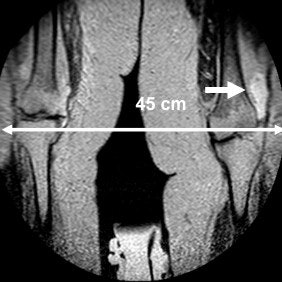

In the May edition of European Radiology, de Bucourt and his colleagues describe their experiences of evaluating 26 excessively obese patients in an open MRI system with a 250-kg table weight capacity, 40-cm gap, and a width of 160 cm. CT, conventional MR, and ultrasound exams were impossible or inconclusive in these patients, who had a body mass index greater than 35 and an average age of 46. All exams were performed on a 1-tesla Panorama high-field open system (Philips Healthcare) with a lightweight, vertical field, superconducting magnet, and a built-in solenoid technology transmit/receiver quadrature body coil (Eur Radiol, May 2011, Vol. 21:5, pp. 1004-1015).